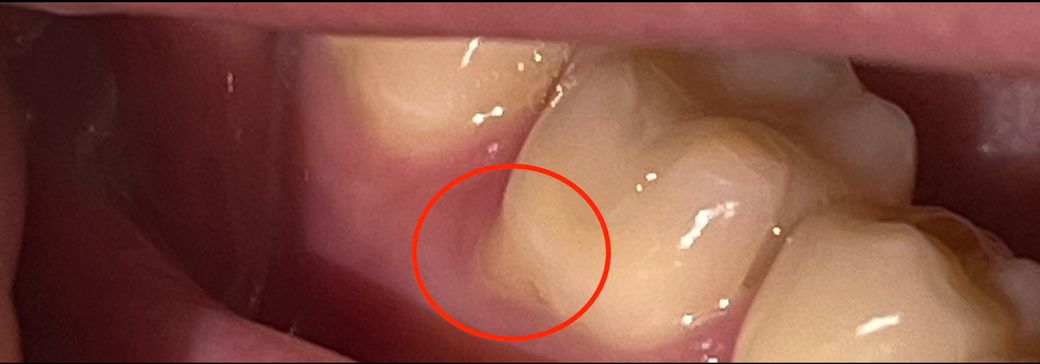

위 사진에 동그라미 쳐진 치아가 2년전쯤 인레이한 치아임. 일요일부터 갑자기 가만있을 때 욱신한 느낌이 살짝 들어서 뭐지 하고 봤는데 검은색으로 보이는 충치나 이런건 없어서 이러다 말겠지 했는데 계속 아팠어요.

근데 오늘 갑자기 거울 봤는데 사진처럼 치아 밑부분에 살짝 색깔 다른 부분이 보여서 눌러봤는데 살짝 아파요..

해당 부위는 마모증이 생긴 것으로 보입니다 마모증으로 인해서 치아 내부 구조인 상아질이 노출이 되면 시린 느낌이 들고 해당 부위를 만들 때 통증이 있을 수 있습니다.

마모증은 너무 과도한 의미가해져서 생기는 것이기 때문에 양치질을 할 때 약한 힘으로 치아가 난 방향으로 양치질을 해주는 것이 좋습니다.

• 안녕하세요 치과의사 김철진입니다. 저부위는 치경부 마모증인거 같습니다. 치경부 마모증은 잇몸이 내려가서 치아의 뿌리가 노출되서 시린증상이니 레진으로 떼우시는 치료를 하시면될것같습니다.

• 사진의 해당 부위는 잇몸이 퇴축되면서 치아 뿌리부분이 드러난 것입니다 색상이 다른 것은 치아 머리부분의 바깥쪽을 이루는 법랑질, 뿌리 부분을 이루는 백악질의 색상차이입니다